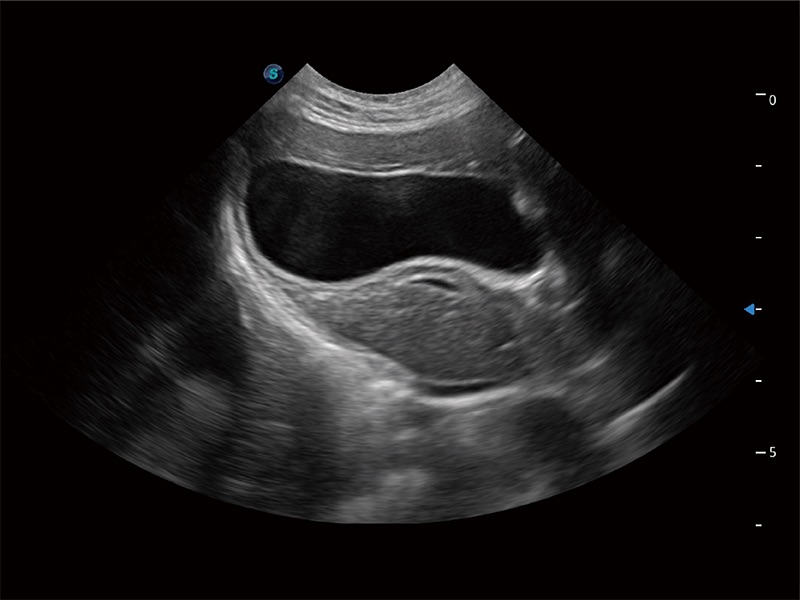

动物是人类最亲密的朋友和最值得信赖的伙伴。九州酷游也一直致力于探索动物专用的超声影像解决方案。全新推出的ProPet系列,是九州酷游在动物超声影像智能化、专业化、精准化的一次跨越式革新。动物不能用言语来表述自己的不适,通过超声影像,ProPet系列搭建了动物医生与不同物种沟通的“桥梁”,为动物医生注入了“治愈之力”。 ProPet 80 是九州酷游匠心打造的一款高端动物专用彩超,采用性能卓越的全新硬件架构,极大提升超声系统的运行效率和数据处理能力,帮助动物医生从容应对日益增多的挑战性病例和日益多样化的临床需求。

高性能和先进的临床应用工具可以为动物医生提供临床信心。ProPet 80 搭载了先进的腹部和浅表应用工具,帮助医生在日常临床实践中发挥前所未有的作用。